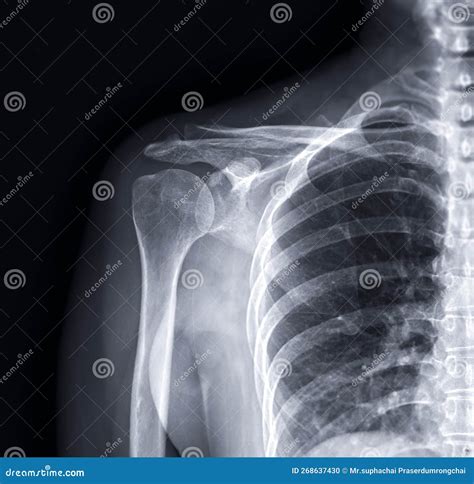

The X Ray Shoulder Joint Procedure

The X Ray Shoulder Joint procedure involves several steps to ensure accurate imaging:

1. The patient is positioned in front of the X-ray machine, usually standing or sitting.

2. The technician may ask the patient to move the arm into different positions to capture various angles of the shoulder joint.

3. Multiple images are taken to provide a comprehensive view of the shoulder, including the front, side, and top views.

4. The entire process typically takes about 15-20 minutes.

During the procedure, it is important for the patient to remain still to avoid blurring the images.